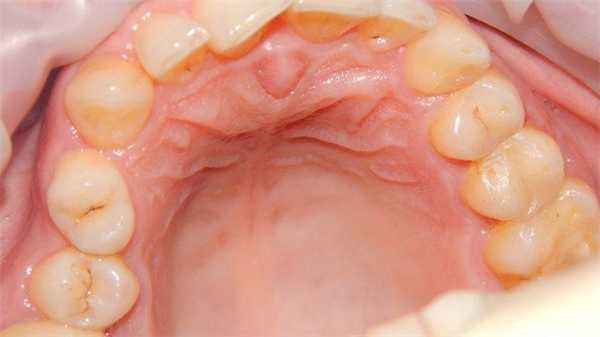

Растут кисты резцового канала медленно, безболезненно, редко достигая больших размеров. Проявляются они обычно после разрушения небной кости в виде полушаровидного эластического выпячивания, расположенного по средней линии костного неба позади центральных резцов. Иногда кисты впервые обнаруживаются при нагноении, и тогда клиника их напоминает небный абсцесс. Пациенты могут не на что не жаловаться или предъявляют жалобы на отек твердого неба, иногда боль, при вовлечении в патологический процесс сосудисто-нервного пучка могут возникать парастезии в области papilla incisiva. При росте в вестибулярном направлении киста может вызывать резорбцию зубов и их смещение.

При осмотре полости рта в переднем отделе нёба по его середине может определяться безболезненное округлой формы образование с четкими границами. При пальпации отмечается «зыбление». Центральные резцы челюсти, как правило, интактные, электровозбудимость пульпы в пределах нормы. При рентгенологическом обследовании обнаруживается разрежение костной ткани округлой формы в области резцового отверстия. Контуры периодонтальной щели центральных резцов сохранены. Вместо нормального резцового отверстия при этом находят очаг просветления костной ткани овальной или округлой формы, расположенный по средней линии. Киста резцового канала, в отличие от одонтогенной кисты, располагается строго по средней линии. Если же она проецируется на корни зубов, то в этих случаях всегда на фоне просветления кости можно обнаружить периодонтальную щель зуба. Кистой следует именовать расширение резцового отверстия более 0,6 см. Кисты резцового канала необходимо отличать от радикулярных кист верхних центральных резцов Решающим диагностическим методом является КЛКТ-обследование.

Женщина 46-ти лет, явилась на профилактический осмотр. В анамнезе хронический медленно прогрессирующий генерализованный пародонтит взрослых. Жалоб нет. НА ОПТГ отмечался участок рентгенпрозрачности округлой формы с четкими границами, 1.4 см в диаметре в проекции корней 1.2, 1.1, 2.1, 2.2 зубов. ЭОД вышеуказанных зубов 3-5 мкА, зубы интактны, перкуссия безболезненная, определялась физиологическая подвижность. Далее дифференциальная диагностика проводилась со следующими заболеваниями: киста носонёбного канала, увеличение носонёбного канала, гигантоклеточной гранулемой, фолликулярной кистой сверхкомплектного зуба, примордиальной кистой, назоальвеолярной кист. Было выполнено КЛКТ-исследование, что и позволило поставить диагноз киста носонебного (резцового) канала.